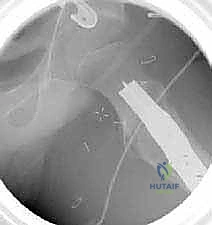

6. التثبيت الداخلي القوي (Internal Fixation)

لضمان التحام العظم في وضعه الجديد، يستخدم الدكتور هطيف نظام تثبيت عالمي يتمثل في صفيحة الشفرة الزاوية (AO 90-degree Blade Plate) أو مسامير وصفيحة مخصصة للأطفال. يتم إدخال الشفرة في عنق الفخذ، وتثبيت الصفيحة على جسم العظم باستخدام براغي معدنية قوية.

7. الإغلاق والتعافي

يتم التأكد من الاستقامة النهائية ومجال الحركة الميكانيكي للمفصل، ثم تُغلق الأنسجة والجلد بخياطة تجميلية دقيقة لتقليل الندبات.